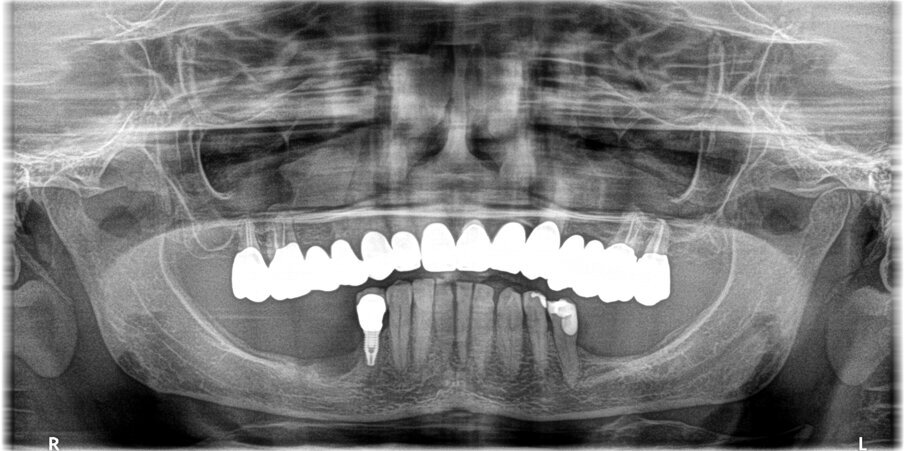

La paziente donna di 72 anni in buono stato di salute generale si presentò alla nostra attenzione per la mancanza dei denti nei settori inferiori posteriori (Fig. 1). Dalla radiografia OPT si notava che nel settore 4 era presente una zona di radiotrasparenza causata dalla recente perdita di due impianti dentali a causa di periimplantite. Si decise pertanto di iniziare a ripristinare il settore 3 (Fig. 2).

Dopo l’esecuzione di esame CBCT della zona (Figg. 3, 4), si evidenziò che la quantità d’osso al di sopra del nervo alveolare era esigua e inoltre la mandibola presentava un grosso sottosquadro. Si pianificò l’inserimento di due impianti dentali BTI CORE da 4,5 mm di lunghezza e 3,75 mm di larghezza.